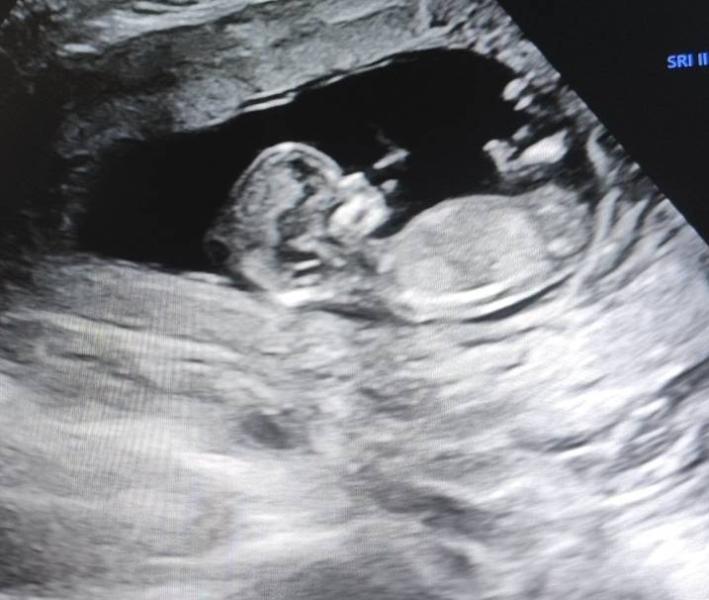

Что ж, первый скрининг позади) пол не предположили, буду ждать второй скрининг 🙂

Если хотите, можете скинуть самое первое узи и я скажу кто там))

Я тут уже многим наговорила. У кого-то совпало, у кого-то жду гендер пати😄